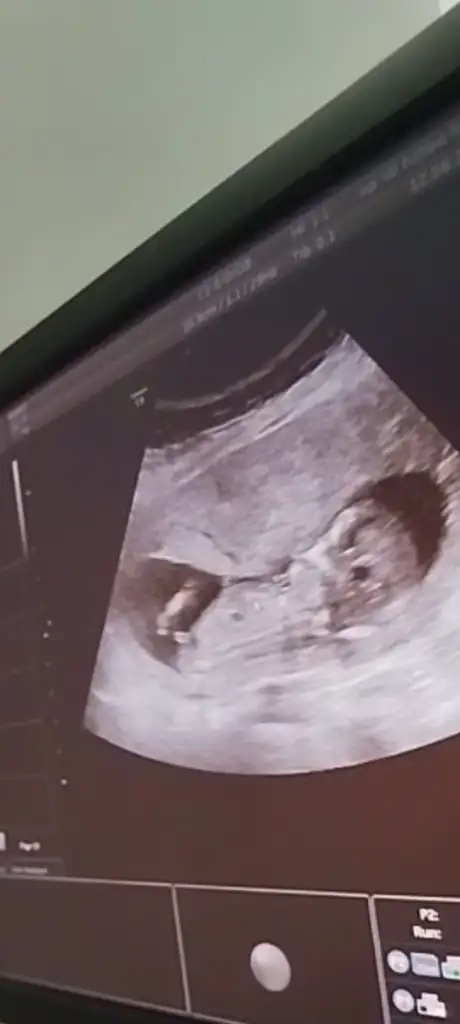

12 haftalık, sizce bizim cinsiyetimiz nedir?

12 haftalık, Bizimki nedir sizce?Erkek gibi geldi bana kesin olmamakla beraber. Sağlıkla gelsin inşallah

Erkek12 haftalık, sizce bizim cinsiyetimiz nedir?

Erkek bence12 haftalık, Bizimki nedir sizce?